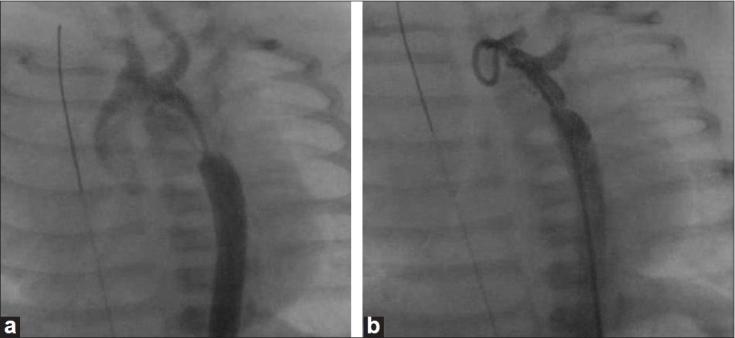

We reviewed data of 10 infants (mean age of 2.9 +/-1.6 weeks) who underwent catheter intervention for severe coarctation and left ventricular (LV) dysfunction between July 2003 and August 2007. Additional cardiac lesions were present in 7. Mean systolic gradient declined from 51+/-12 mm Hg to 8.7+/-6.7 mm Hg after dilation. The coarctation segment was stented in five patients. Procedural success was achieved in all patients with no mortality. Complications included brief cardiopulmonary arrest (n =1), sepsis (n = 1) and temporary pulse loss (n = 2). LV dysfunction improved in all patients. Average ICU stay was 5+/-3.4 days and hospital stay was 6.5+/-3.4 days. On follow-up (14.1+/-10.5 months), all developed restenosis after median period of 12 weeks (range four to 28 weeks). Three (two with stents) underwent elective coarctation repair, two underwent ventricular septal defect (VSD) closure and coarctation repair and one underwent pulmonary artery (PA) banding. Two patients who developed restenosis on follow-up were advised surgery, but did not report. Two (one with stent) underwent redilatation and are being followed with no significant residual gradients.

Balloon dilation +/- stenting is an effective interim palliation for infants and newborns with critical coarctation and LV dysfunction. Restenosis is inevitable and requires to be addressed.

我们回顾了2003年7月至2007年8月期间10例(平均年龄2.9±1.6周)因严重主动脉缩窄和左心室功能障碍接受导管介入治疗的婴儿的数据。7例存在其他心脏病变。扩张后平均收缩期压差从51±12 mmHg降至8.7±6.7 mmHg。5例患者的缩窄段置入了支架。所有患者均获得手术成功,无死亡病例。并发症包括短暂心肺骤停(1例)、败血症(1例)和暂时性脉搏消失(2例)。所有患者的左心室功能障碍均有改善。平均重症监护病房住院时间为5±3.4天,住院时间为6.5±3.4天。随访(14.1±10.5个月)时,所有患者在中位时间12周(4至28周)后均出现再狭窄。3例(2例置入支架)接受了择期主动脉缩窄修复术,2例接受了室间隔缺损封堵和主动脉缩窄修复术,1例接受了肺动脉环扎术。2例随访时出现再狭窄的患者被告知手术,但未进行手术。2例(1例置入支架)接受了再次扩张,目前正在随访,无明显残余压差。

球囊扩张±支架置入术是治疗病情危急的主动脉缩窄和左心室功能障碍婴儿及新生儿的有效临时姑息治疗方法。再狭窄不可避免,需要加以处理。